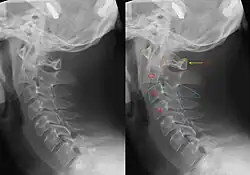

| Tomografia computadorizada apresenta uma fratura do enforcado | |